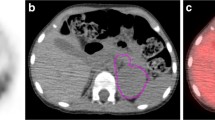

Further evaluate tumor metabolic burden and WMH on survival

Based on the results of multivariate survival analysis, we further investigated the predictive effect of whole-body tumor metabolic burden and WHM. The optimal cut-off values for WMTV, WTLG and WMH were 413.14, 1044.14 and 0.448, respectively, determined by the area under the receiver operating characteristic curve. Significant differences were observed in WMTV and WTLG for PFS (P < 0.001, P < 0.001, respectively) and OS (P < 0.001, P < 0.001, respectively). Similarly, WMH also manifested significant differences for PFS (P < 0.001) and OS (P = 0.004) (Fig. 3). Two representative NB patients with high and low WMH values were presented in Fig. 4.

Two representative NB patients with high and low WMH values; A: a 32-month-old girl with a relatively uniform FDG uptake in whole-body tumor (White arrow, IMH:0.443, WMH:0.470), was disease free survival 51.3 months after diagnosis; B: a 29-month-old girl with a heterogeneous FDG uptake in whole-body tumor (Red arrow, IMH:0.463, WMH:0.392), relapsed at 7.1 months, and died at 8.9 months after diagnosis